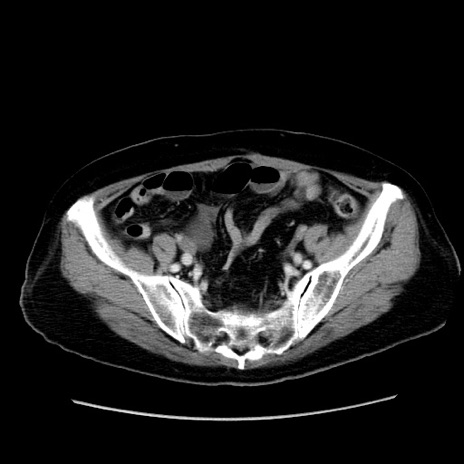

症例19(横断像)

【症例】80歳代女性

【主訴】下腹部痛

【現病歴】約8時間前より下腹部痛の出現あり、救急外来受診。

【既往歴】両側付属器切除

【身体所見】意識清明、下腹部正中に手術痕あり、その部位に一致して圧痛と反跳痛あり。腸蠕動音は亢進。

【データ】WBC 9300、CRP 0.15